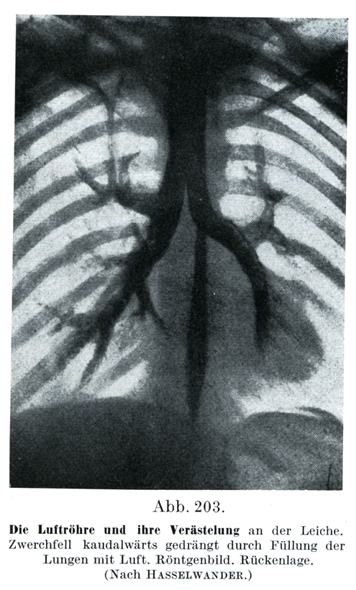

[図203]気管とその分枝(死体)

横隔膜は空気で充された肺によって下方に押しやられている.レントゲン写真.背位(Haßelwanderによる)